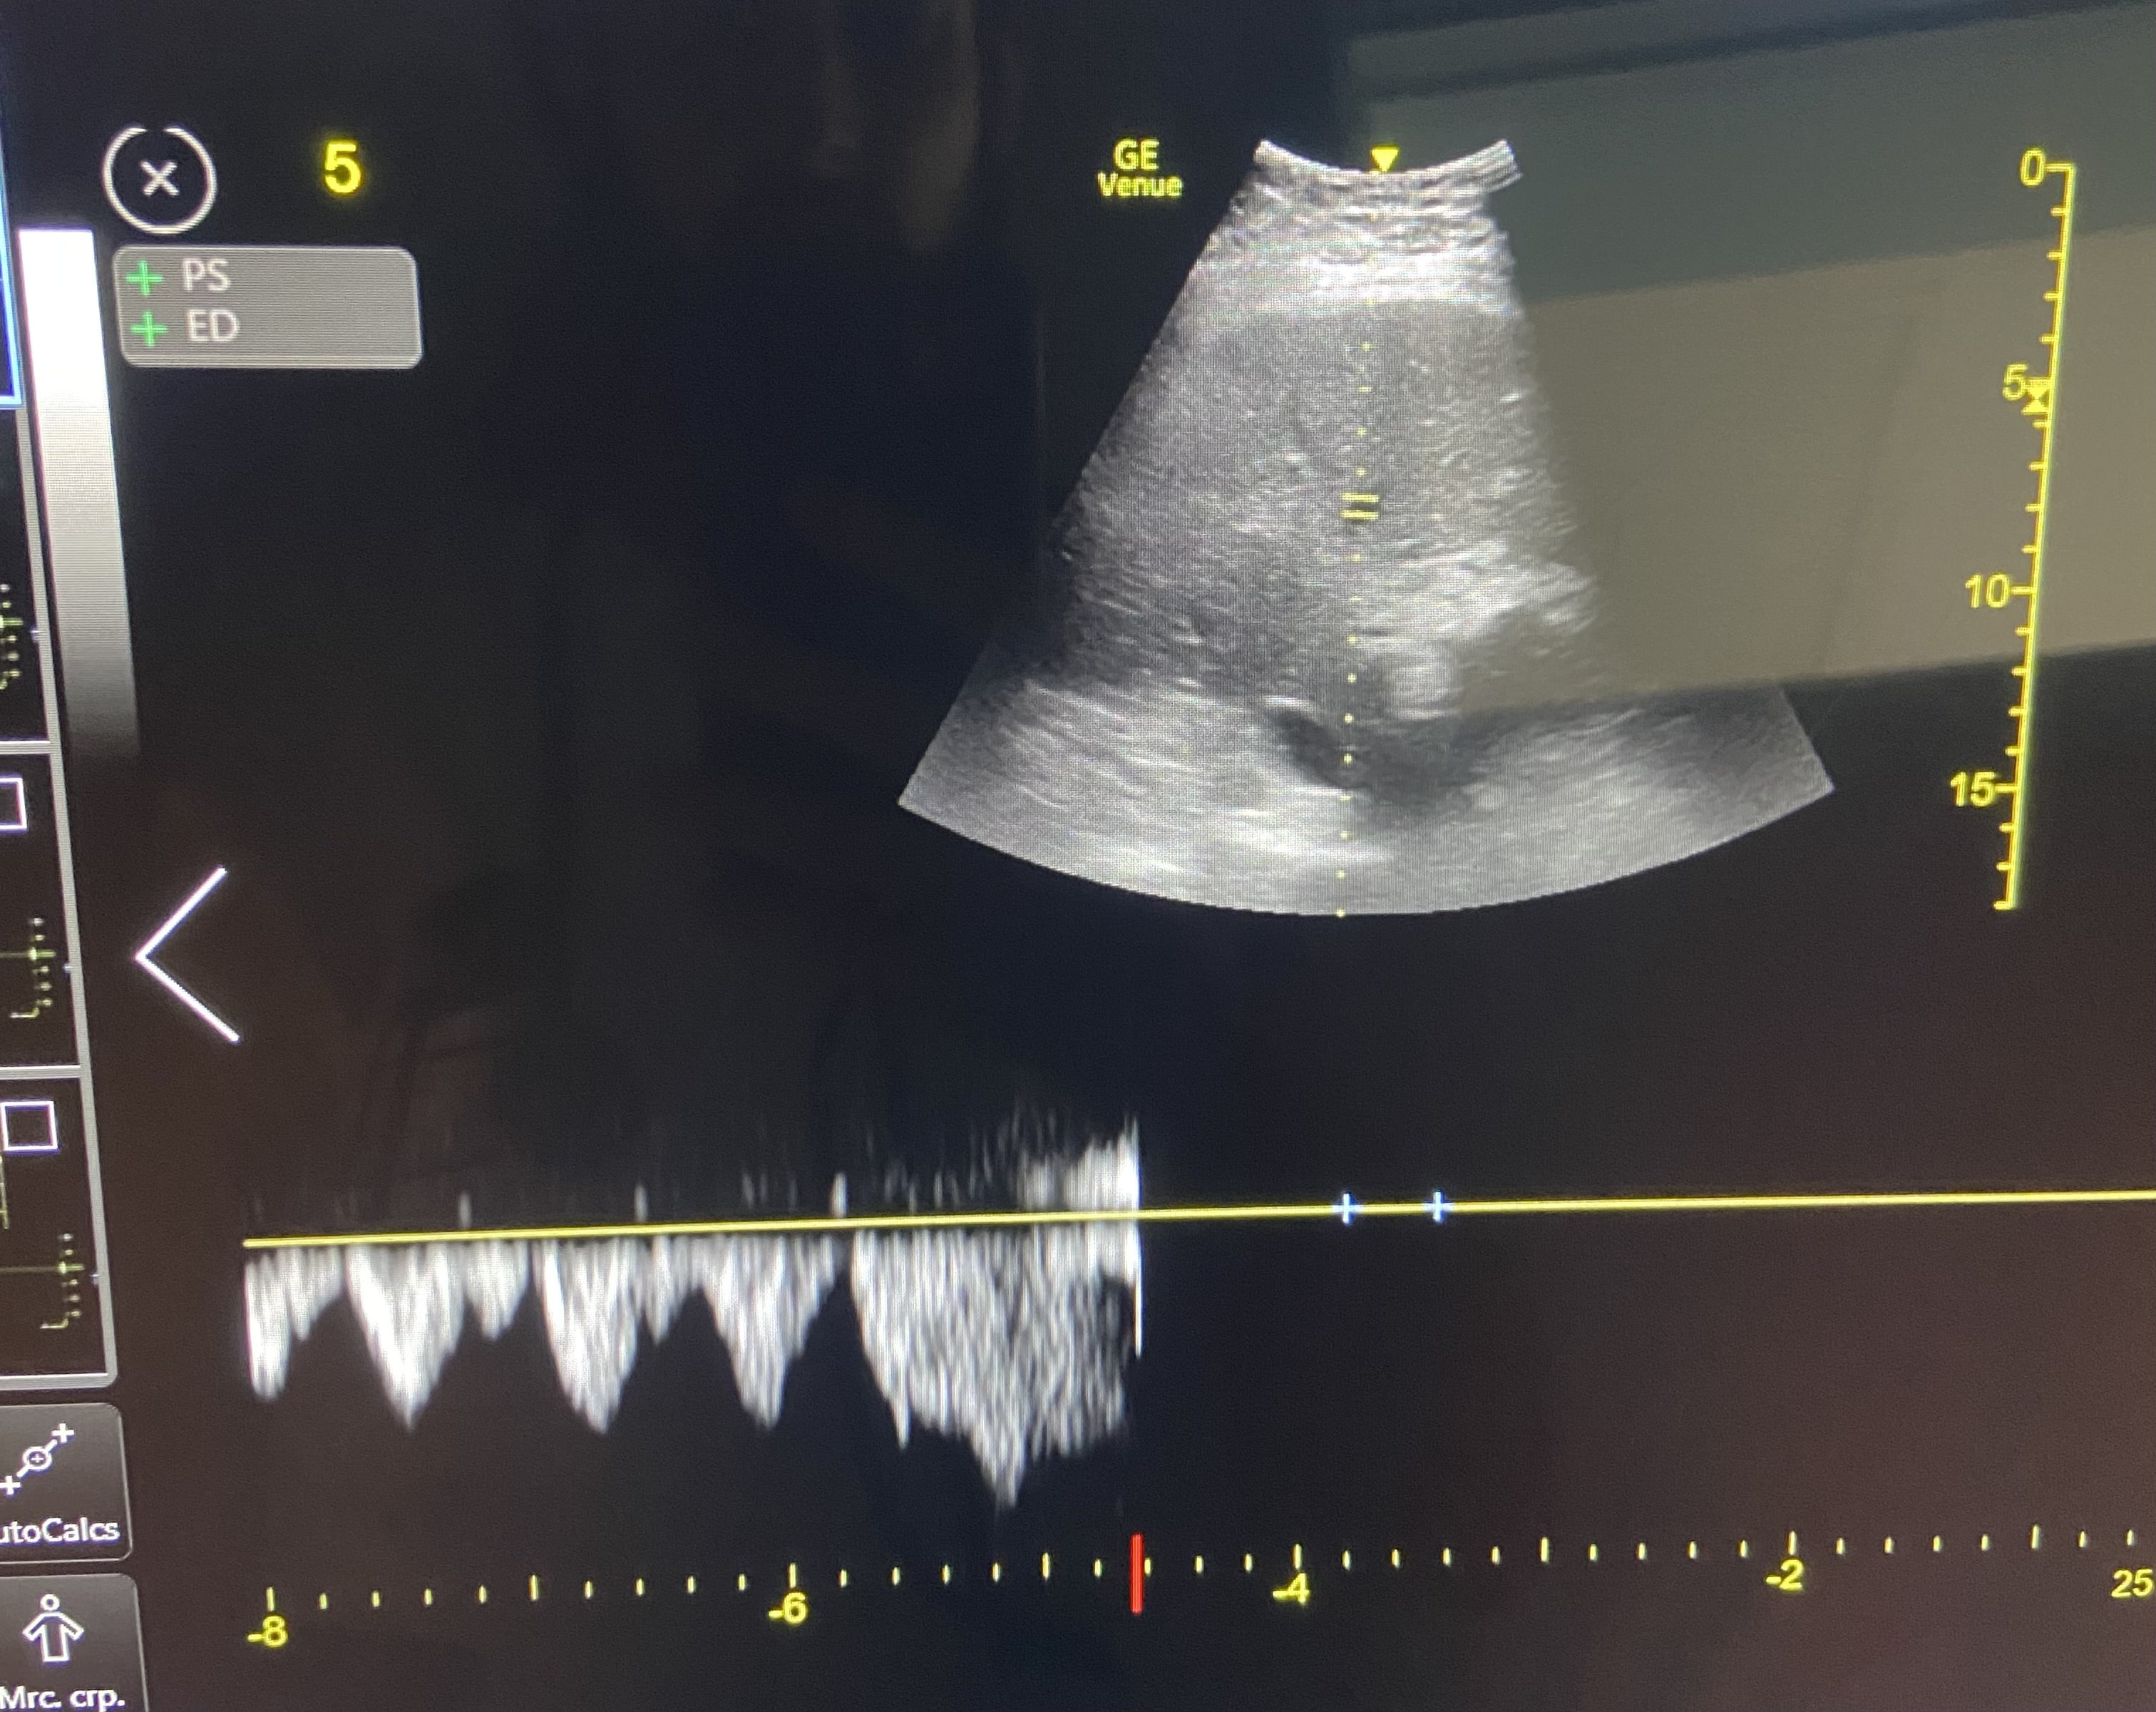

Paciente hombre de 85 años con antecedentes de insuficiencia cardiaca. Acude a urgencias por disnea progresiva de 48 horas de evolución, precedida por 10 días de ingesta deficiente. En la exploración física, presenta crepitantes bibasales hasta campos medios, edemas hasta rodillas, mucosas secas y signo del pliegue positivo. La tensión arterial es de 107/65 mmHg. Los análisis sanguíneos revelaron una creatinina de 1.8 mg/dL y un NT-proBNP de 5500 pg/mL, con una fracción de excreción de urea de 32%, compatible con origen prerrenal. Ante la aparente contradicción, se realiza una ecografía PoCUS dirigida. La vena cava inferior mostró un diámetro máximo de 2,13 cm con colapsabilidad en inspiración, y el Doppler de venas suprahepáticas, venas porta e intrarrenales no evidenció signos de congestión. En conjunto, los hallazgos configuraron un perfil VExUS Grado 1.

Se diagnostica un síndrome cardiorrenal tipo 1. El diagnóstico diferencial se establece entre una otros tipos de síndrome cardiorrenal. La ecografía orientó a una congestión vascular como principal problema a resolver en este caso complejo.

En base al perfil VExUS Grado 1 se inició tratamiento con diuréticos a dosis moderadas para tratar el componente congestivo, sin empeorar el renal.

El paciente mostró una evolución favorable con tratamiento diurético inicial. Una vez hospitalizado, el protocolo VExUS mostró un perfil con menor congestión, por lo que se pudo iniciar fluidoterapia, logrando una normalización de los parámetros renales.

Este caso demuestra que el protocolo VExUS es una herramienta dinámica, esencial para el médico de urgencias en el manejo complejo de la volemia en pacientes cardiorrenales, permitiendo una toma de decisiones segura y eficaz en situaciones clínicas complejas.